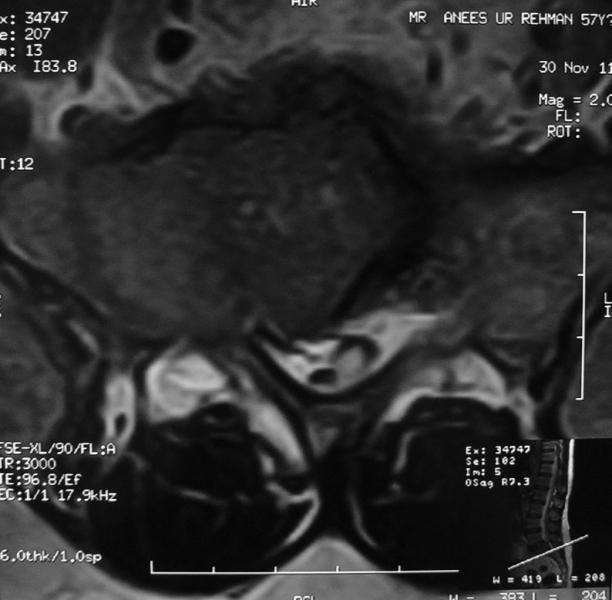

Massive Disc Operated By Micro Surgery